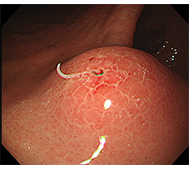

食道がん

- 内視鏡治療 :病変がリンパ節転移の無い早期食道がんに対し、内視鏡治療が行われます。